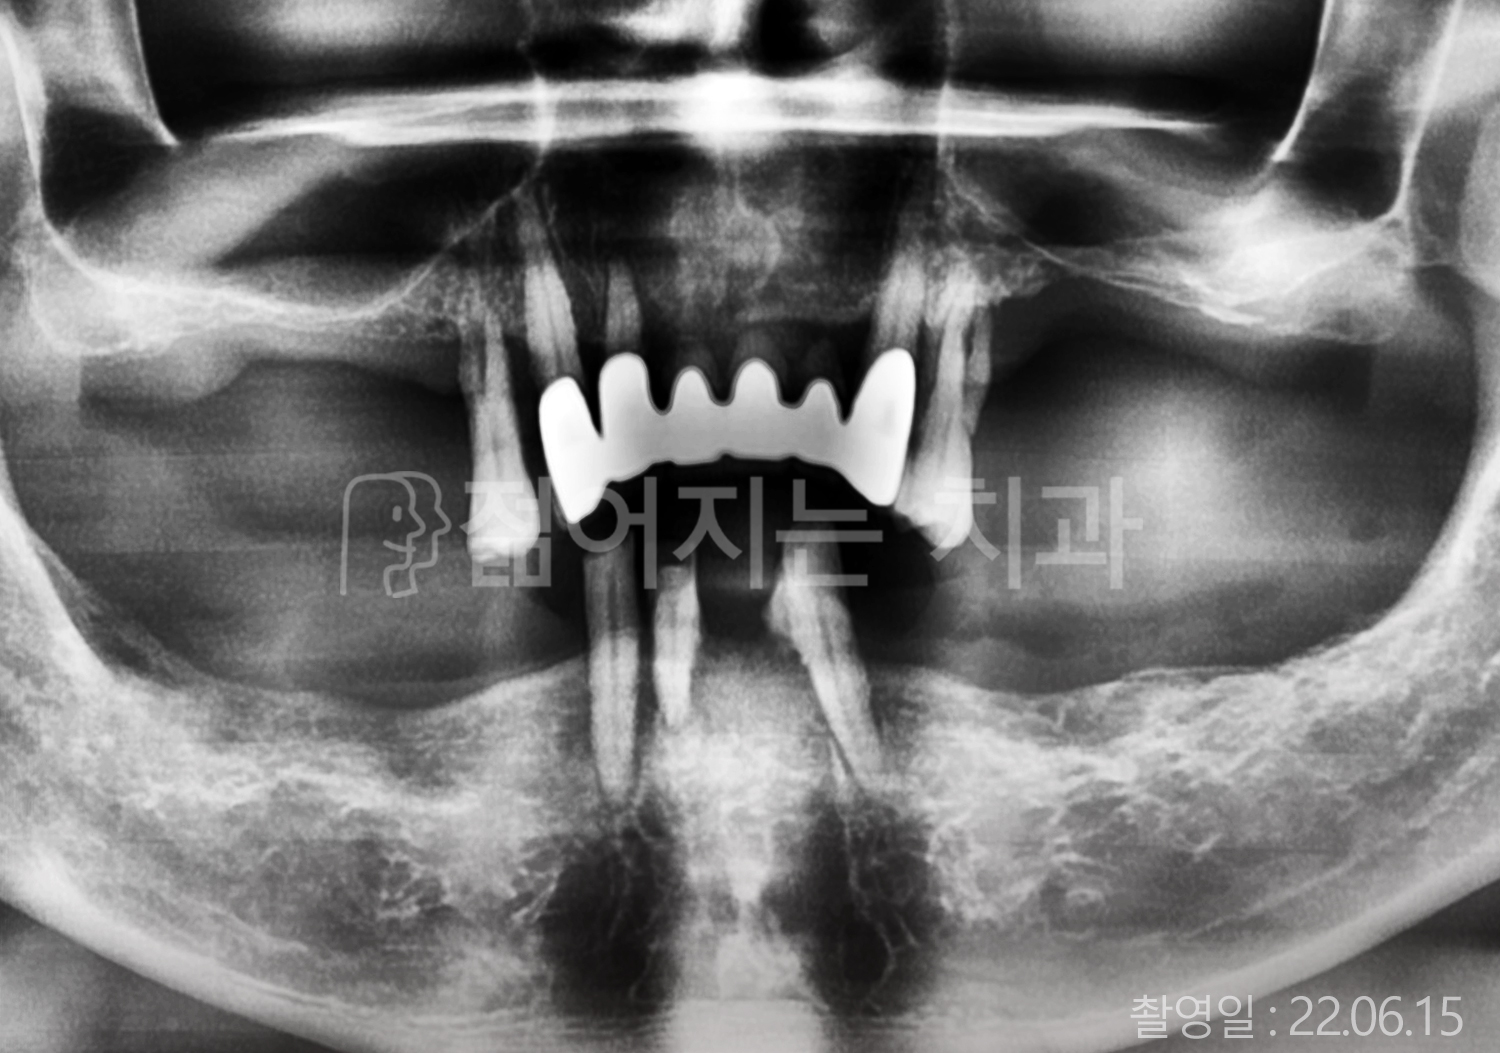

• 50대 전체치아 10개 이상 임플란트